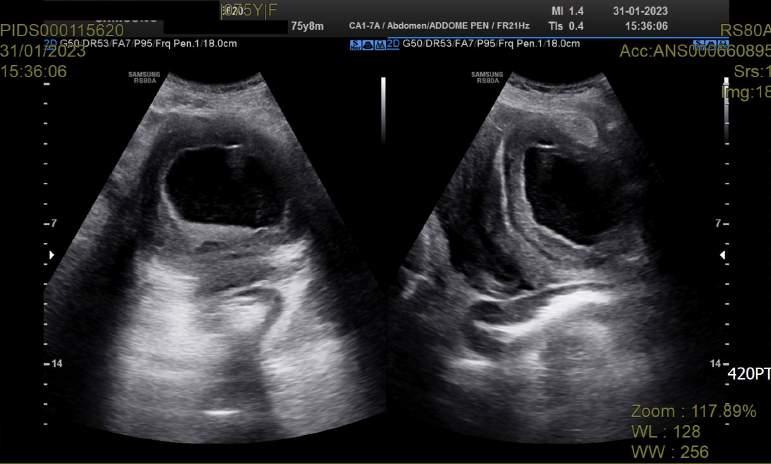

Issuu converts static files into: digital portfolios, online yearbooks, online catalogs, digital photo albums and more. Sign up and create your flipbook.